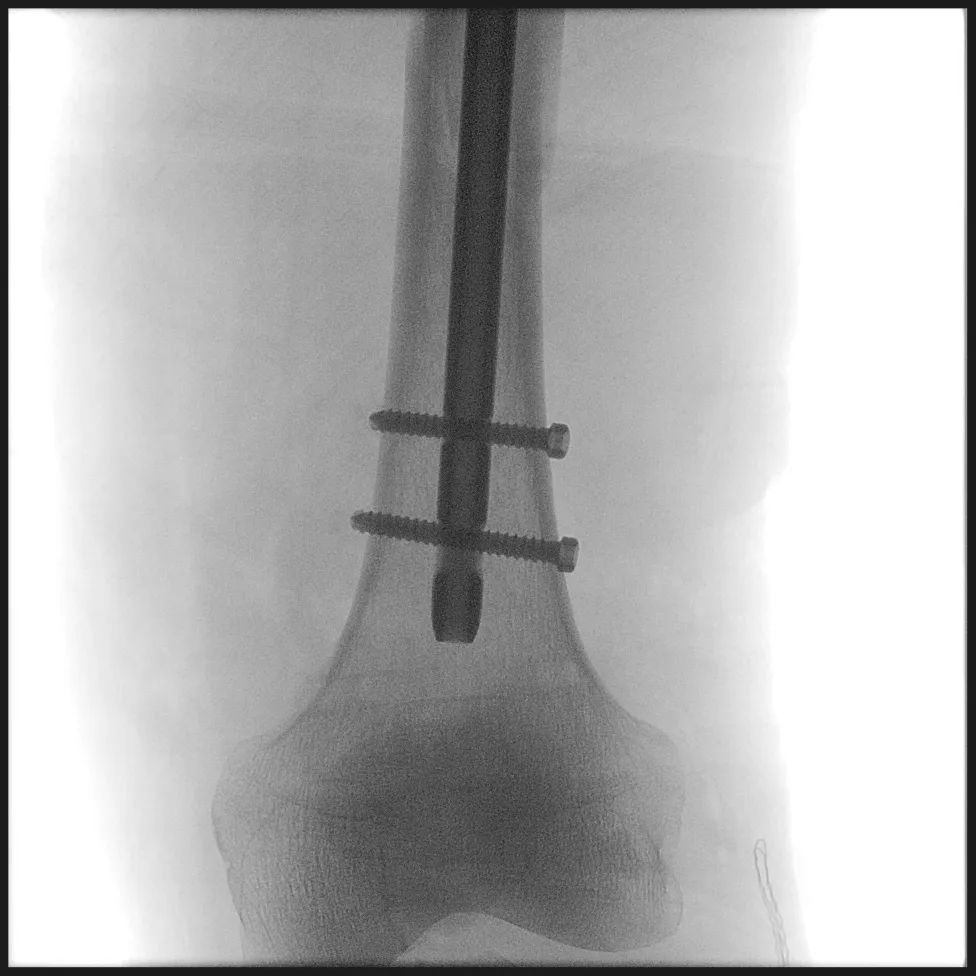

之后,利用该系统的三维导航功能,赵春鹏主任医师实现了髓内钉入钉点的精准导航,顺利插入髓内钉并锁钉,成功完成了对该例股骨骨折的微创治疗。

谈及此次手术的得力“助手”,赵春鹏表示,此次手术使用的骨盆骨折复位机器人是吴新宝副院长带领团队历经10年研发、6年多的产业转化,于去年底刚刚获批的创新医疗器械产品,是全球首创的骨折复位机器人系统,目前已经成功完成100多例骨盆骨折的闭合复位微创治疗,手术效果远超临床专家徒手治疗水平。本次临床试验,是首次将该系统拓展至股骨骨折的闭合复位微创治疗。手术的成功开展,证明该系统具有很强的向下兼容能力,能够应用于更多的骨折微创治疗中,相信未来可以为更多患者带来福音。